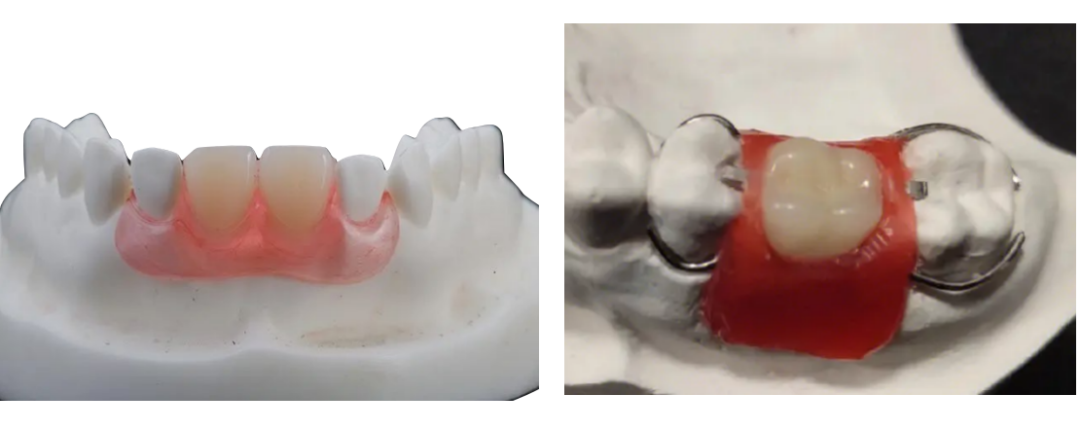

固定-活动联合修复

这种方式集合了固定义齿和活动义齿修复的优点,减少了活动义齿的体积,增加了固位性和舒适性,也要利用其他的牙齿进行预备,以粘接、卡扣等方式套接在基牙上面,这就是活动固定联合修复。

有一些患者只有前牙余留,后牙只剩下一个残根,也可以不拔掉这个残根,保留下来,安装一个磁性附着体,作为活动义齿的固位装置。